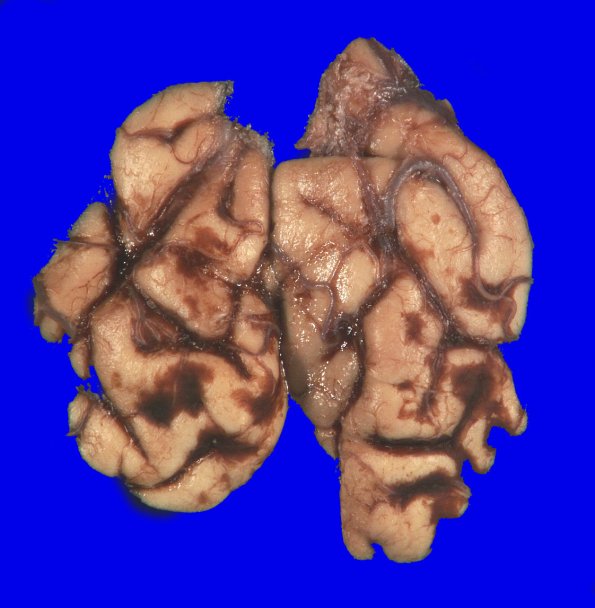

The occipital poles with subarachnoid hemorrhage with a small degree of contusive injury which could be considered contrecoup.